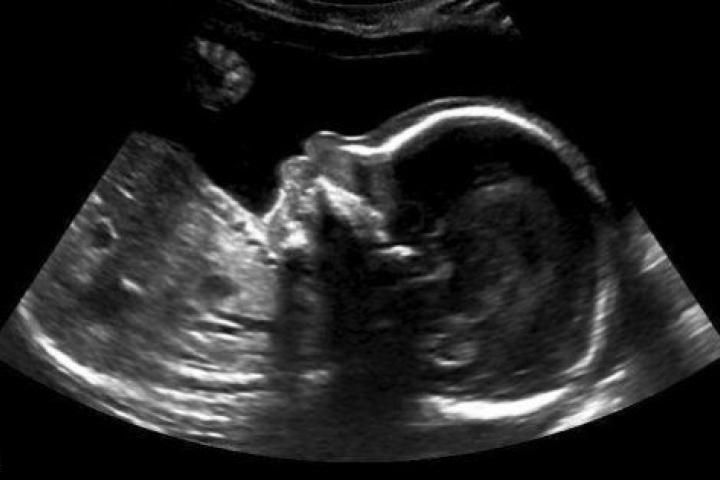

Este bebé tiene un mensaje para sus padres desde dentro del útero

Todavía no ha nacido, pero este bebé canadiense tiene un mensaje para sus padres: quiere decirles que todo va a ir bien.

Nicole Kim, la madre, encontró este inspirador mensaje en la ecografía de la semana 20: un pulgar para arriba. Kim contó en la web del programa Today, de la NBC, que el mensaje del bebé llegó justo cuando su padre, Tony, lo acababan de echar del trabajo.

En una entrevista con el Calgary Herald, Kim contó también que el técnico de la clínica de Calgary donde hizo la ecografía le dio rápidamente al zoom y tomó la foto cuando vio al bebé con el pulgar levantado.